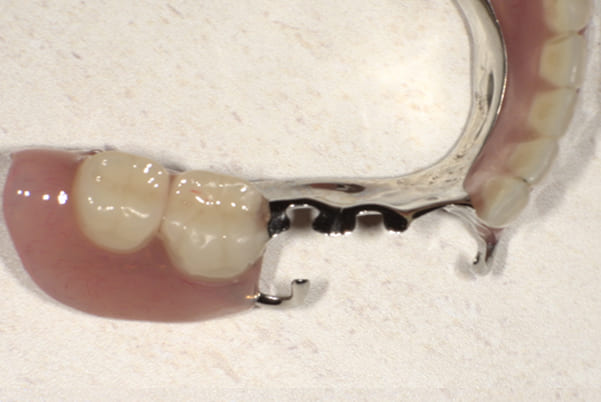

陶材焼着付鋳造冠 ミリングラべット加工

残りの歯が少ない場合は、入れ歯が動きやすく、またご自身の歯にも負担がかかるため、残りの歯の被せ物、入れ歯ともに、歯に負担がかかることを最小限にした特殊な加工を行い、歯を長持ちさせる設計としました。